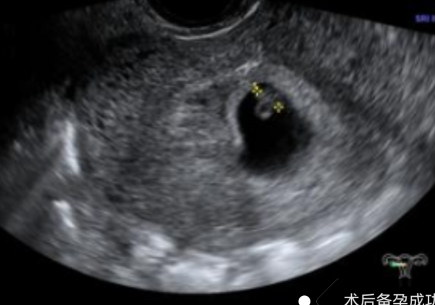

幾個月前,陳女士(化名)突發(fā)不規(guī)則陰道出血癥狀,且出血持續(xù)多天未見緩解,身體不適與生育焦慮雙重壓力下,前往我院就診,尋求專業(yè)診療方案。不規(guī)則陰道出血是婦科臨床的高頻癥狀,其背后病因復雜,可能潛藏著子宮內(nèi)膜息肉、黏膜下肌瘤、子宮內(nèi)膜增生等多種病變。若未能及時明確診斷并采取干預措施,不僅會嚴重影響患者日常生活質(zhì)量,更可能對生育功能造成不可逆的潛在威脅。針對該患者的病情,婦科胡菊英副主任帶領婦科團隊展開全面評估,最終確定宮腔鏡手術為最佳診療方案。該技術無需開刀,可經(jīng)人體自然腔道進入2025-11-10